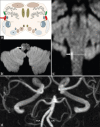

Lateral medullary syndrome encompasses a broad spectrum of symptoms and signs depending on the bulbar localization of the lesion. Body lateropulsion (BL) can occur without vestibular and cerebellar symptoms, as a unique manifestation of a lateral medullary infarction. However, it is relatively rare and challenging to diagnose. We report a case of a 72-year-old woman who presented with a tendency to fall to the right. She denied having vertigo, cerebellar signs, sensory loss, or motor weakness. No signs of vestibular dysfunction were found on the ENT examination. Neurological evaluation was unremarkable, except for mild ataxia of the right limbs along with BL to the right side when standing and walking. Brain magnetic resonance (MR) imaging showed an acute small infarct in the right lateral aspect of the medulla extending from the rostral to the caudal level. MR angiography found no stenosis or vascular occlusions. We believe that ipsilateral axial lateropulsion shown by our patient may be related to a selective ischemic lesion of the dorsal spinocerebellar tract in its medullary course. A lateral medullary infarction should be seriously considered in patients who present with isolated BL without further signs of bulbar involvement.